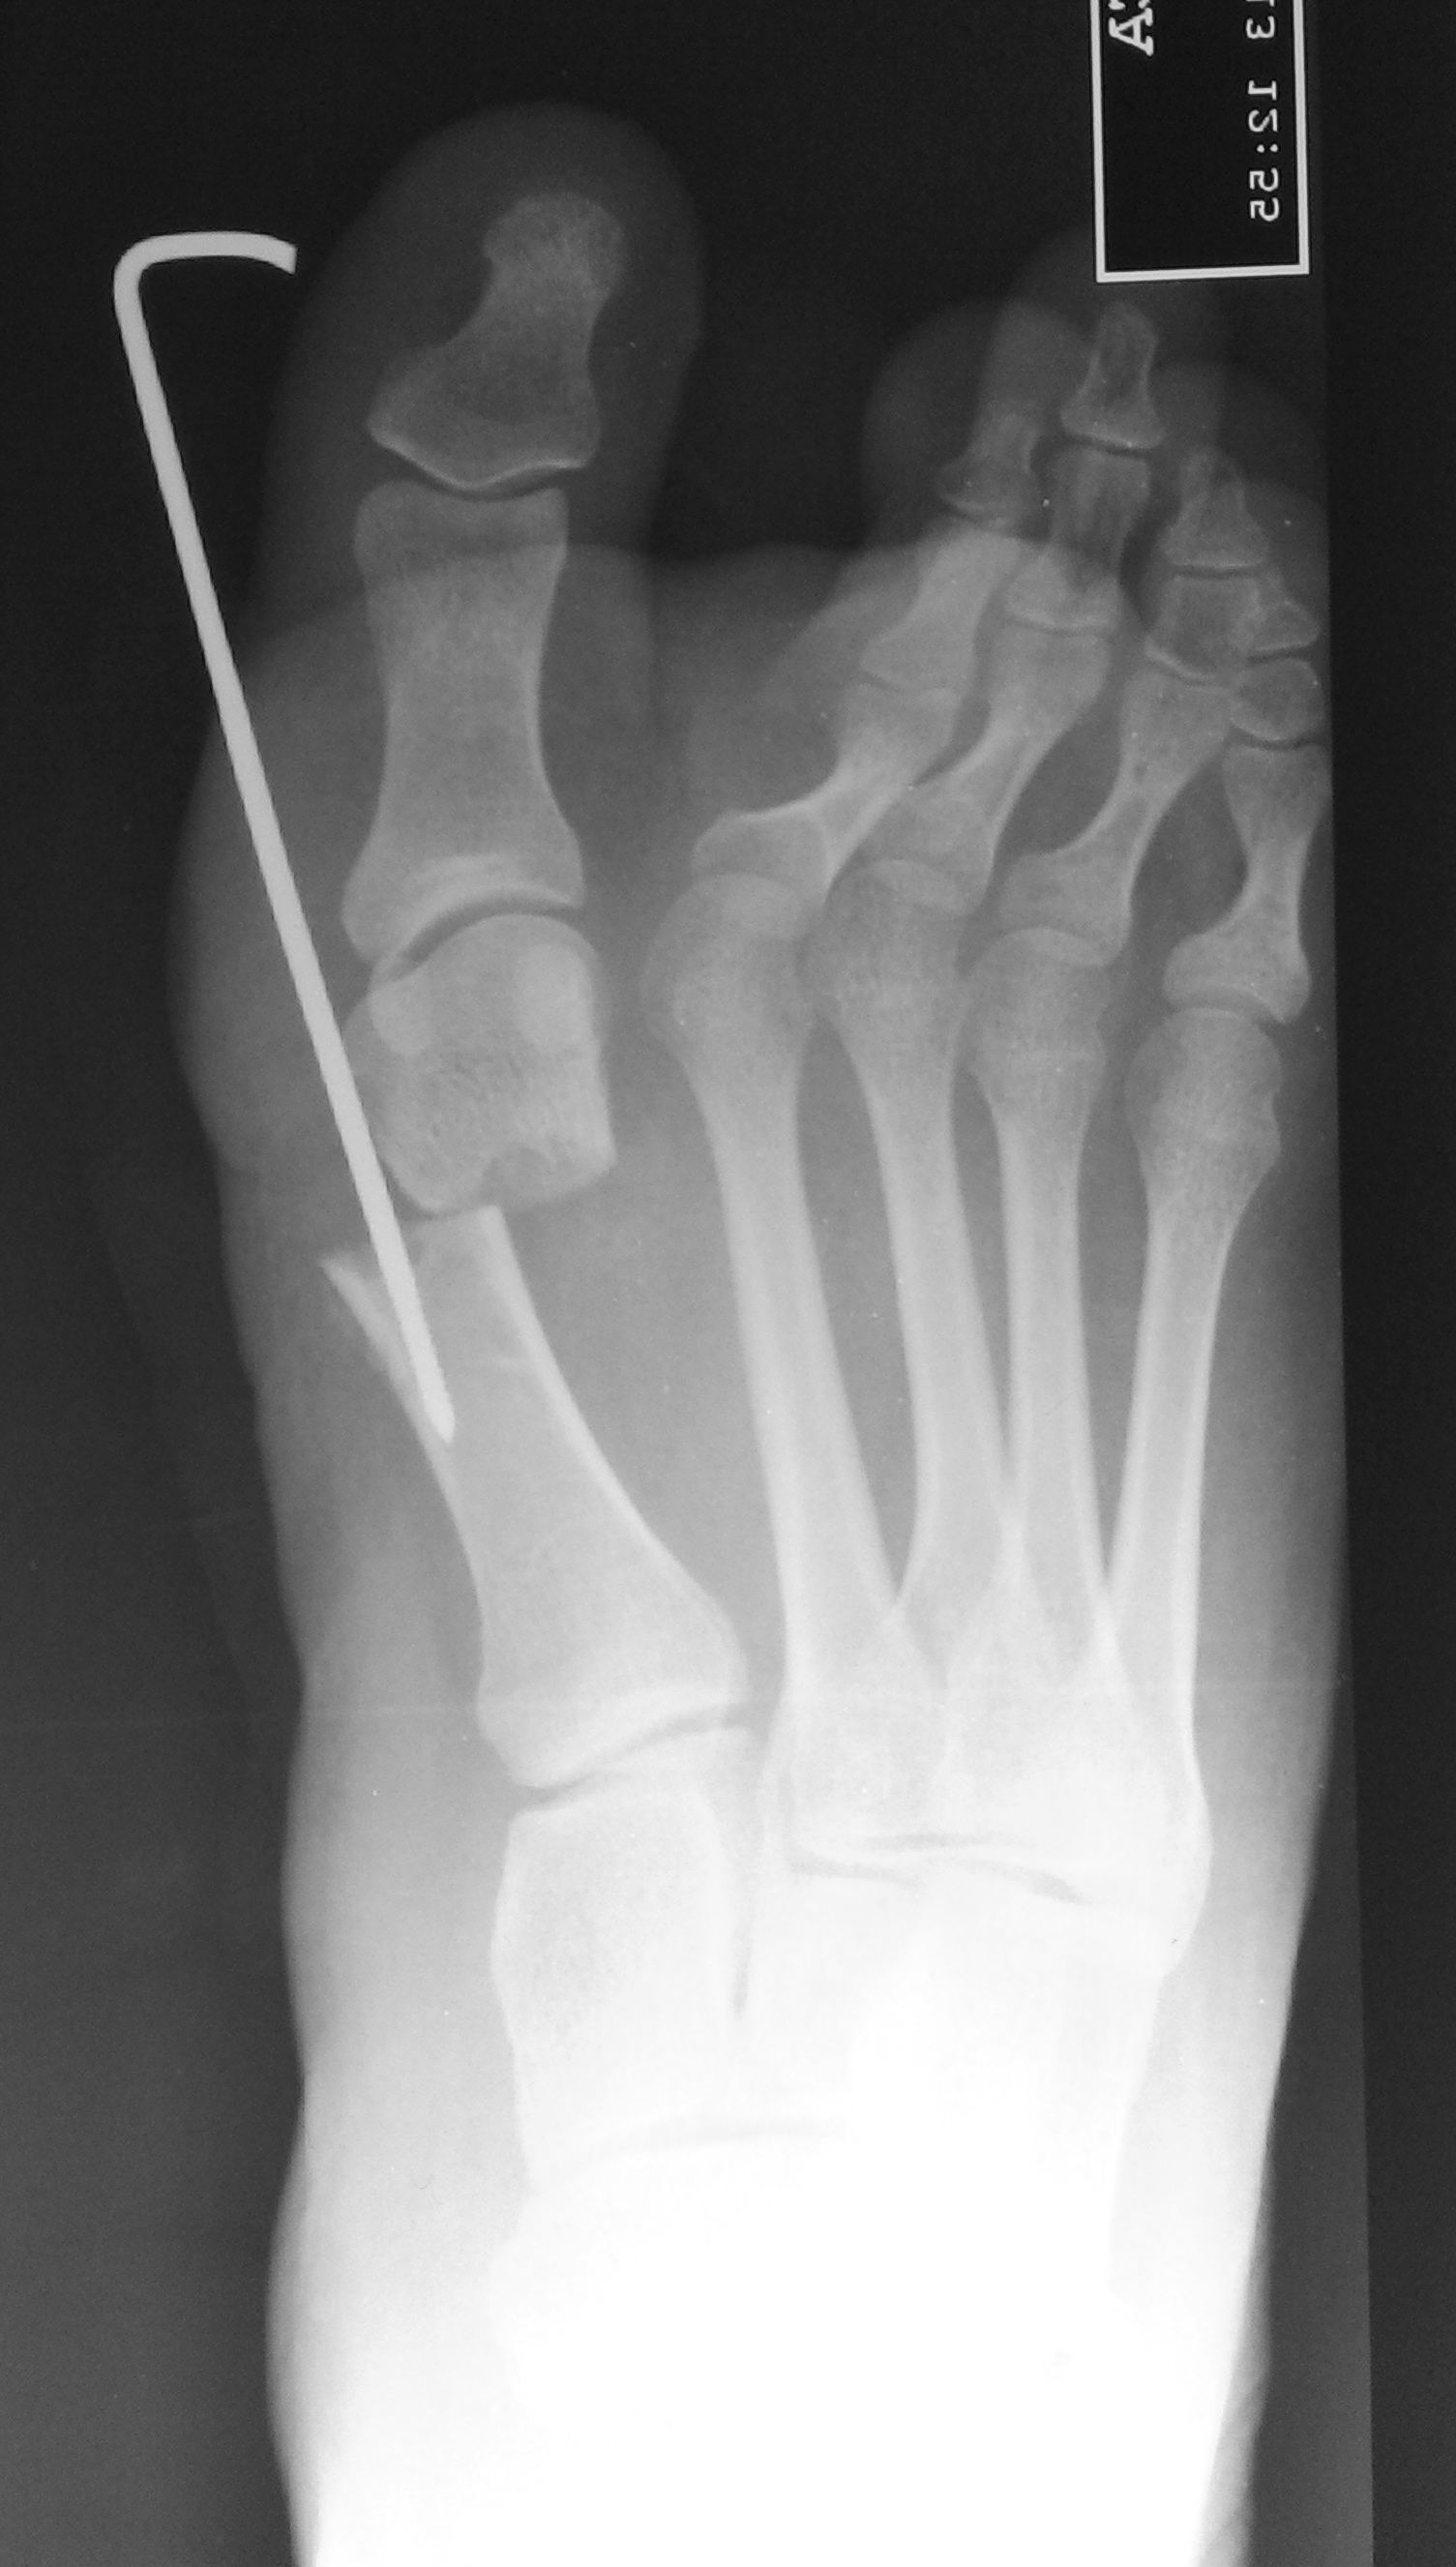

Osteotomía percutánea de Bosch ¿El paciente acepta la clavija? Análisis clínico – funcional y resultados a corto plazo. [Bosch percutaneous osteotomy. Does the patient accept the nail? Clinical and functional analysis and short-term result.]

8 Bösch P, Markowski H, Rannicher V. Technik und erste ergebnisse der subkutanen distalen metatarsale-I-osteotomie. Orthopädische Praxis 1990;26:51-6.

19 Bösch P, Wanke S, Legenstein R. Hallux valgus correction by the method of Bösch: a new technique with a seven-to-ten-year follow-up. Foot Ankle Clin 2000;5:485-98.